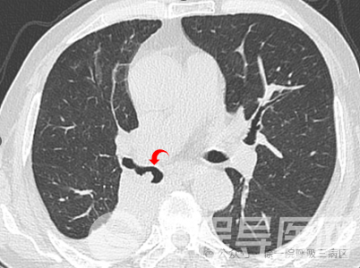

全程导医网 徐州就医信息:近日,一位73岁的李大爷因近5天出现咳嗽、咳痰、气喘症状,入住徐州市第一人民医院呼吸与危重症医学科三病区,此前该患者曾明确诊断为“右肺鳞癌”,曾行“卡铂+紫杉醇”化疗及“替雷利珠单抗”免疫治疗。入院后,复查胸部CT提示右肺下叶支气管狭窄、闭塞,右肺下叶肺不张、实变。

在呼吸与危重症医学科三病区主任崔文洁的主持下,副主任施海和副主任医师陈云峰相互协作,为患者实施全麻硬质支气管镜下冷冻治疗。术后李大爷咳嗽、咳痰及憋喘症状得到明显改善。

为保证手术顺利实施,科室为李大爷制定了缜密的手术方案及应急预案,与麻醉科密切协作,充分做好术前准备及评估。4月18日,施海和陈云峰相互配合,置入硬质支气管镜、应用圈套器切除突出病变、应用冷冻探头及活检钳清理残余病变、清理积聚的分泌物......约30分钟手术结束。整个过程,患者生命体征平稳,术后状态良好,无特殊不适。